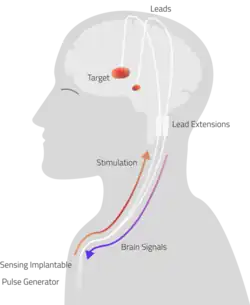

Deep Brain Stimulation (DBS)

Another invasive surgical treatment of essential tremor is deep brain stimulation (DBS). DBS is a surgical procedure that involves the placement of a permanent electrode with 4-8 contacts within the brain with connecting wires connected to a pulse stimulator implanted near the patient's collarbone.[65] In the treatment of tremor, the electrodes are placed in the ventral intermediate nucleus (Vim) of the thalamus.

The pulse stimulator delivers constant electrical pulses to the target area, which interfere with activity of the target area, which has been shown to improve tremor symptoms.[91] At one year following the surgical intervention with DBS, patients showed 66% improvement and 48% improvement at 10 years.[80] DBS is considered an effective surgical treatment of ET, but there are associated side effects and complications that have been reported with DBS in clinical trials, including imbalance or gait instability, dystonia, paresthesia, hemorrhage.[79]